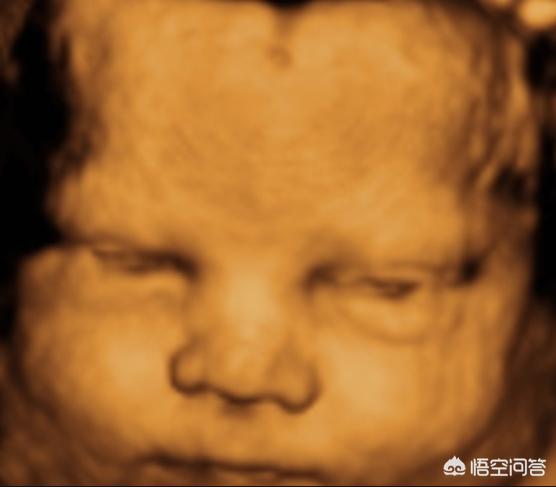

以前孩子出生后好几天才睁眼可能有以下原因:

1. 早产

如果宝宝在26周以前早产 , 眼睛是肯定睁不开的 。 但是不用担心 , 到了矫正26周以后 , 宝宝的眼睛慢慢就能够张开了 。

2. 产程过长

以前都是顺产 , 很多产妇要花特别长的时间生产 , 宝宝生出来的时间过长 , 耗费的体力也特别多 , 出来之后 , 特别累 , 很快就睡着了 , 也就是为什么不马上睁眼的原因 。 同时因为产程过长 , 产道的挤压也会让眼睛过度浮肿 , 也让宝宝没有办法马上睁眼 。

现在有很多孕妇都是剖腹产 , 宝宝基本上没有消耗体力 , 出来之后警惕性特别高 , 也会出现马上睁眼的情况 。 这个新世界 , 需要多看看!

3. 营养不足